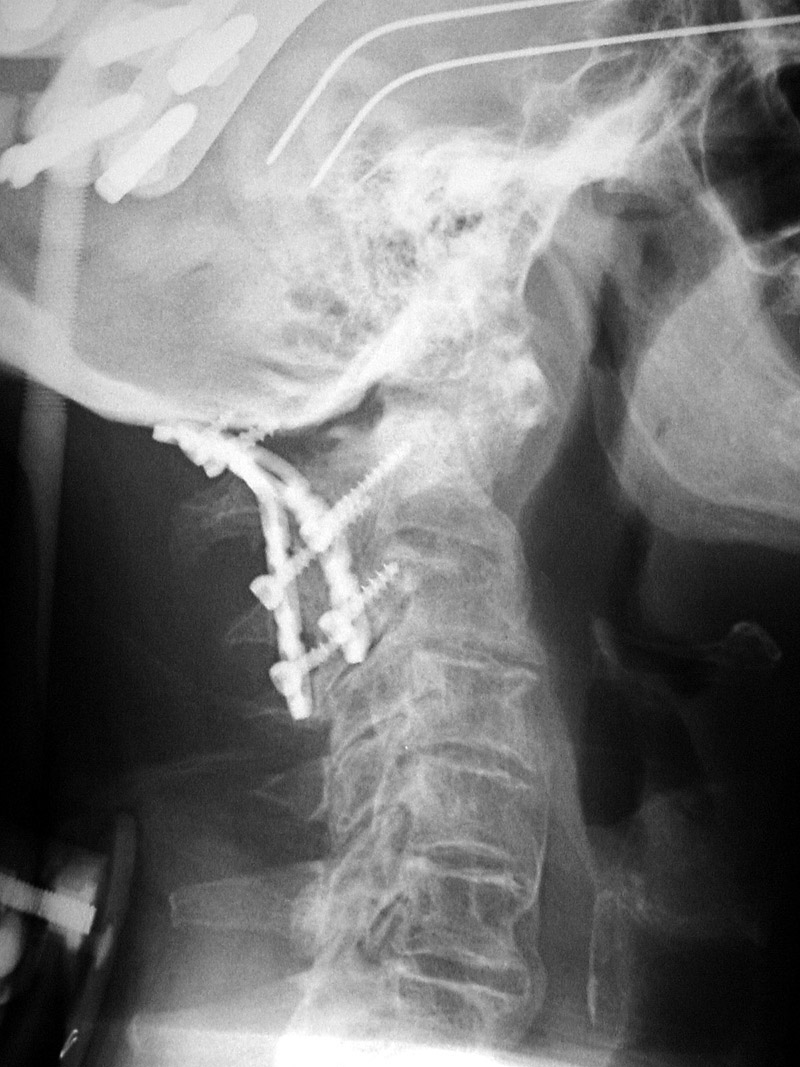

Odontoid screw (nail) AP view Odontoid screw (nail) lateral view Odontoid screw (nail) fracture fixation with posterior cervical fixation plates and screws [extension view] Odontoid screw (nail) fracture fixation with posterior cervical fixation plates and screws [flexion view]

Odontoid screw AP view Odontoid screw lateral view Odontoid screw (nail) fixation with posterior cervical plates and screws Odontoid nail flexion view

There is also an anterior cervical fusion plate and screws from C3-6.